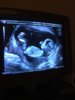

Ktory to tydzień?A o to moja piłeczka ktora mieści cale 3,5cm człowieka